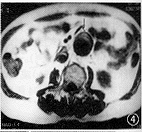

图1,2 图1为SE左前斜位,示主动脉弓部囊状突出,内无信号;图2为三维增强磁共振血管造影(3D DCE MRA)左前斜位,示左锁骨下动脉开口以远可见囊状突出,其内信号与主动脉弓相同,手术证实为假性动脉瘤 图3,4 图3为3D DCE MRA冠状位,示腹主动脉扭曲,肾动脉水平以下瘤样扩张,左肾动脉起始部局限性重度狭窄,双侧髂总动脉多发狭窄和扩张;图4 为SE轴位,示腹主动脉扩张,其内可见新月形附壁血栓,手术证实为真性动脉瘤伴附壁血栓 图5,6 图5为数字减影动脉血管造影(IADSA)冠状位,示腹主动脉扭曲延长,双肾动脉水平以下呈囊状扩张,左肾动脉起始部局限性重度狭窄,右肾动脉起始部局限性轻度狭窄;图6为3D DCE MRA冠状位,除与图5相同表现外,还可见双侧髂总动脉、髂内、外动脉多发狭窄伴扩张,管腔不规则 图7,8 图7为3D DCE MRA冠状位,示双侧髂总动脉及髂内、外动脉多发狭窄,右侧桥血管通畅,与髂总动脉吻合处轻度狭窄;图8为IADSA冠状位,除与图7相同表现外,侧支血管显示较3D DCE MRA佳

病变组34例 3D DCE MRA与IADSA或(和)手术结果对照,符合率分别为胸腹主动脉100.0%(12/12例) (图1~6),髂动脉87.5%(7/8例)(图7,8),颈动脉80.0%(4/5例),头臂动脉75.0%(3/4例),肾动脉60.0%(3/5例),总的符合率为85.3%,主动脉及其主支病变则分别为100.0%和77.3%。与IADSA或(和)手术结果对照的34例病人3D DCE MRA显示假阴性2例,16例正常组中假阳性2例,误诊率8.0%;其敏感性、特异性和准确性分别为94.1%、87.5%和92.0%。

全组中主动脉成像20例,包括主动脉瘤、主动脉夹层等16例(胸和腹主动脉分别为11和5例),其中12例有IADSA或(和)手术对照,诊断符合率100%。3D DCE MRA 同SE和梯度回波(GE),能正确显示动脉瘤瘤体大小、主动脉夹层的真假腔和内膜片,鉴别假腔内附壁血栓或慢血流,主动脉狭窄范围和程度,且3D DCE MRA显示主动脉病变与头臂和肾动脉等主支的关系优于SE和GE,可为手术提供重要信息。但不能直接显示瘤体内的附壁血栓大小、范围、主动脉管壁结构以及其与周边脏器的解剖关系,但MRI的SE或(和)GE技术能弥补其不足。因此从整体效果上3D DCE MRA对主动脉疾患的诊断可与IADSA媲美。同时本法无需动脉插管,属微创技术。